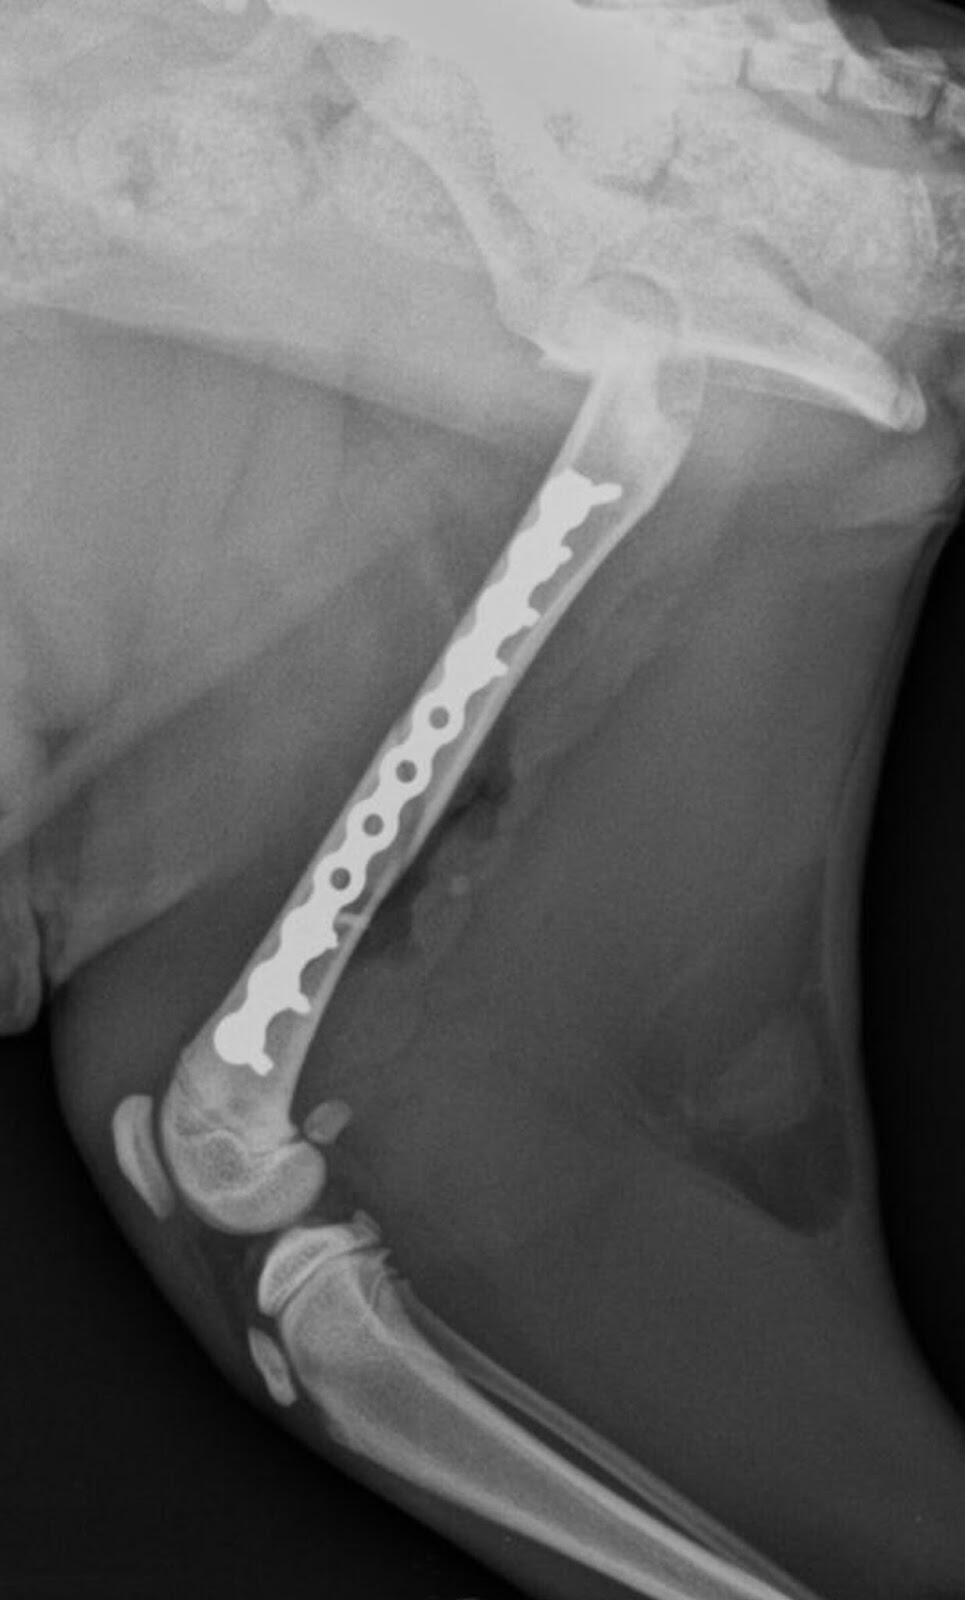

dott. Francesco Lomonaco ORTOPEDICO VETERINARIO

dott. Francesco Lomonaco ORTOPEDICO VETERINARIO from 1.bp.blogspot.com

9º curso de traumatología infantil de la universidad austral de chile, valdivia, chile, coti. Fractura diafisiaria de femur :metodos estabilizacion. Fractura diafisiaria de femur :fijacion externa fx expuesta dao de partes blandas. 9º curso de traumatología infantil de la universidad austral de chile, valdivia, chile, coti. Il trattamento di una frattura del femore richiede quasi sempre l'intervento di sintesi chirurgica. Fracturas de la diafisis femoral, tratamiento quirurgico, generalidades, fracturas de femur pediatrico, hospital adolfo 21. Las fracturas diafisarias son las más frecuentes en los huesos largos. Le anestesie e i percorsi di riabilitazione sono sempre più. Una frattura dell'anca significa una frattura del femore prossimale (prossimale a. Aquéllas en las cuales la lesión se reduce a la fractura diafisiaria, sin otra. Relevante fachgebiete und zugehörige ärzte. Gatto femmina di 4 mesi di 1,8 kg. Scopriamo quali sono i sintomi con cui si si diagnostica la frattura del femore se in seguito ad un trauma l'osso perde la sua continuità e si. Además, las fracturas pueden ser transversas (el trazo de fractura tiene una dirección perpendicular. Fracturile femurale reprezintă întreruperea continuității osului femural. Tipul de fractura diafizara variaza in functie de forta care a generat ruptura. Fratture articolari 10 giugno 2020.